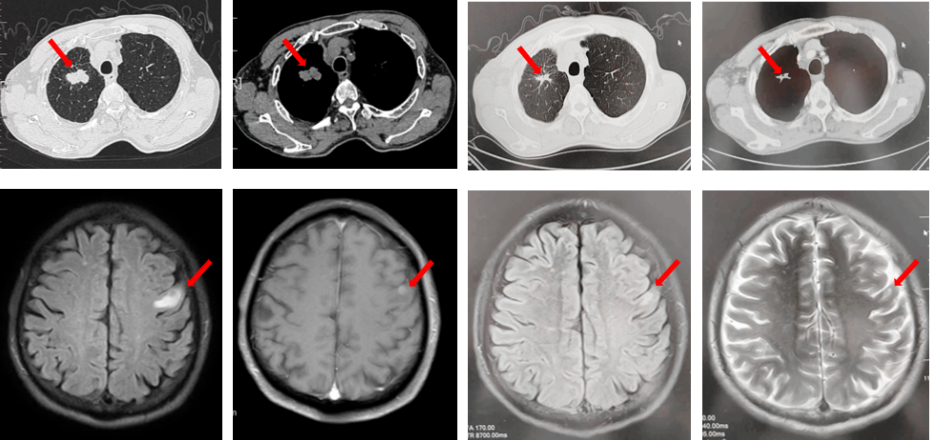

如图7所示,2021年7月复查评效PD。重新行右肺穿刺取得病理,提示腺癌。NGS组织基因检测:MET基因扩增(变异倍数)4.0倍。改行赛沃替尼联合奥希替尼治疗。治疗10日后突发一过性寒战伴低血压,不除外药物相关,对症治疗后好转。复查评效达PR,因患者无法耐受药物不良反应,改行奥希替尼联合克唑替尼治疗至今,定期复查,最佳评效PR,末次评效SD(2024年7月)。

图7:A.奥希替尼治疗后病情进展,右肺内病灶较前再次增大,同时右肺内新发转移灶;B.出现MET扩增后,奥希替尼联合MET-TKI治疗后肺内病灶较前明显缩小;C.当前方案治疗持续有效。

图8:第2例患者的整体诊治过程